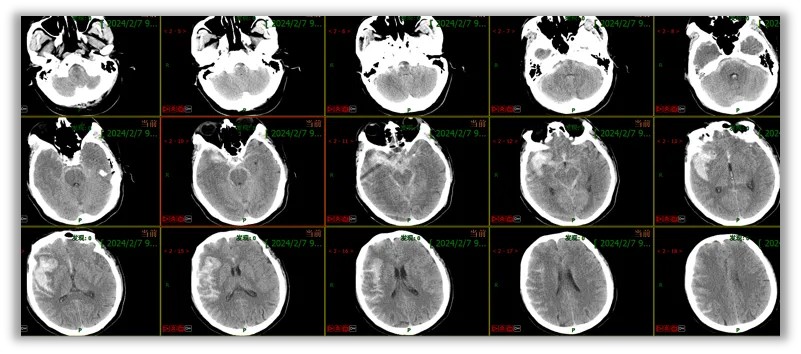

患者男性,69岁,主诉:突发意识丧失2小时,急诊入院。

患者约2小时前在买饭时突发意识丧失,伴恶心、呕吐,随后被送往当地医院,给予对症处理后被120送至我院急诊科,急诊科给予行颅脑CT及CTA示:蛛网膜下腔出血,右侧大脑中动脉瘤,脑室积血。急诊以“脑动脉瘤破裂伴蛛网膜下腔出血”收入院。

颅脑CT及CTA:蛛网膜下腔出血,右侧大脑中动脉瘤,脑室积血;Fisher分级3级。

入院时CT:广泛蛛网膜下腔出血,右侧裂血肿,三、脑室积血;CTA:右侧大脑中分叉部动脉瘤。